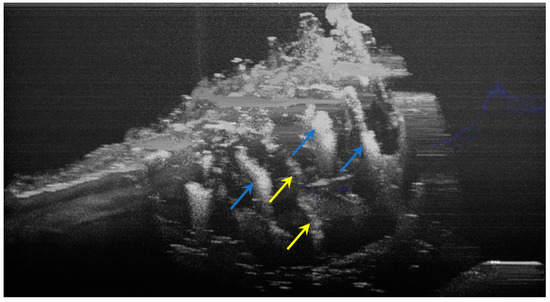

The image processing using ImageJ software showed the spatial disposition and extent of the hypomineralization lesions and hypoplasia (Figure 6, Figure 7, Figure 8 and Figure 9).

Figure 8.

Three-dimensional OCT reconstruction (in ImageJ) of a hypoplasia lesion (Axis 0Y). The yellow arrows indicate a continuous area characterized by the absence of signal, similar to the appearance of a dental crack or fracture.